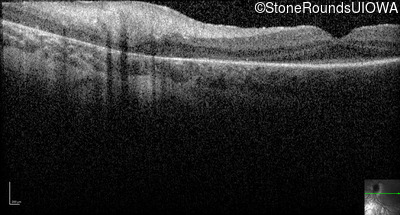

Optical Coherence Tomography - Left -

Light Perception

Exemplar

Expanded OCT Stack

×